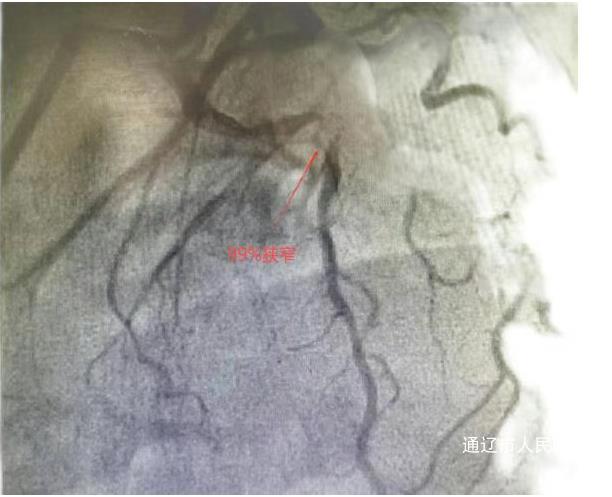

次日,心血管内三科团队采用经桡动脉微创介入技术,在血管内超声(IVUS)引导下为患者手术。术中造影显示其冠状动脉前降支狭窄达99%伴血栓形成,血管动脉硬化较重伴迂曲钙化。团队运用多种先进技术,历时65分钟成功植入两枚药物支架。术后李奶奶胸痛缓解,次日可下床活动,4月16日康复出院。患者及家属对治疗效果非常满意,通过快手平台发布感谢视频,真实记录就医全过程,视频获得近10万点播量,家属在视频中感谢医护人员创造奇迹并感谢医护人员的精心治疗和照顾。